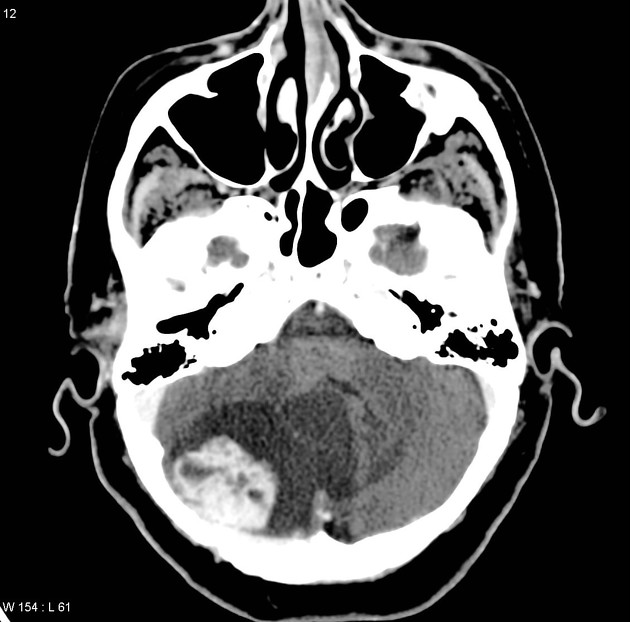

1 — RM de encéfalo com contraste

- T1 axial e sagital sem contraste.

- T2 FSE e/ou FLAIR para parênquima.

- DWI/ADC.

- Pós-contraste: T1 multiplanar (axial, coronal, sagital) com cobertura da fossa posterior.

- Incluir angio-RM (TOF) quando houver suspeita de malformação vascular.